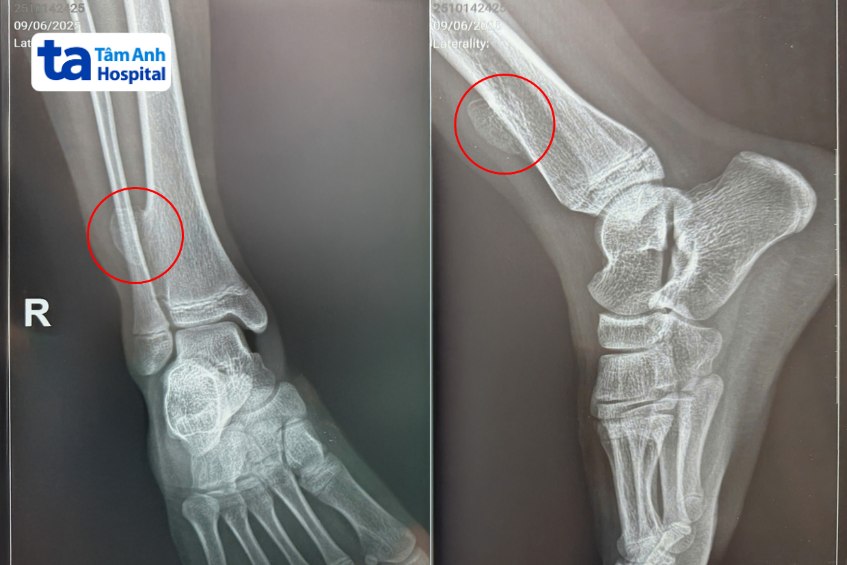

Bé Thảo có niềm đam mê thể thao, từ 10 tuổi đã tích cực tham gia các giải chạy marathon. Vài năm trước, bé tự phát hiện cạnh mắt cá chân ở bên phải có u nhỏ. Khoảng một năm nay, khối u bắt đầu phát triển, kích thước lớn hơn mắt cá chân, không đau nhưng khiến bé thiếu tự tin và lo lắng. Gia đình tìm hiểu, quyết định đưa bé đến Bệnh viện Đa khoa Tâm Anh TP.HCM để khám. Kết quả chụp X-quang và MRI ghi nhận bé Thảo bị u xương sụn ở đầu dưới xương chày bên phải, kích thước khối u khoảng 3x3cm.

BS.CKII Nguyễn Đức Tuấn, Trưởng khoa Ngoại nhi, Bệnh viện Đa khoa Tâm Anh TP.HCM, cho biết, u xương sụn thường là tổn thương bề mặt xương lành tính, đa phần xuất hiện ở xương dài, đầu dưới hoặc đầu trên của xương đùi/ xương chày hoặc xương cánh tay. Tình trạng này thường được ghi nhận ở trẻ trong tuổi dậy thì. Nguyên nhân cụ thể chưa được xác định, tuy nhiên nhiều giả thuyết cho rằng trong độ tuổi phát triển, một số trẻ có sự tăng trưởng quá mức ở những vị trí đầu xương dẫn đến u xương sụn. Trường hợp kích thước u lớn nếu không phẫu thuật sớm có thể dẫn đến lệch trục chi gây ảnh hưởng hình thể và vận động, thậm chí có nguy cơ hóa ác tính.